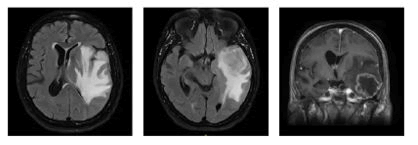

Extended studies, including neuroimaging, were ordered. A non-contrast cranial CT scan described a mass under study with left frontoparietal hypodensity, perilesional edema, and midline shift, suggesting a primary CNS lesion, probable GBM. An MRI with contrast was requested, which revealed a heterogeneous nodular lesion predominantly hyperintense on T2 and FLAIR sequences and hypointense on T1, with ring enhancement after intravenous contrast administration and hemosiderin signs on susceptibility-weighted imaging. The lesion measured approximately 41.7 × 40 × 36.5 mm (AP × T × L), associated with diffuse adjacent vasogenic edema, mass effect, and obliteration of the subarachnoid spaces. There was partial obliteration of the left lateral ventricle and approximately 8 mm midline shift to the right. Hyperintense images on T2 and FLAIR sequences were also observed in the periventricular and subcortical white matter of the bilateral frontal and parietal lobes, related to chronic microangiopathies. The conclusions were: (1) Left temporal space-occupying lesion, suggestive of high-grade glioma (glioblastoma multiforme); (2) Extensive vasogenic edema and local mass effect with subfalcine herniation. Neurosurgery considered that the patient required a left temporal tumor resection guided by neuro-navigation (Figure 1).

XXXXXXXX

Figure 1: Cranial CT scan.